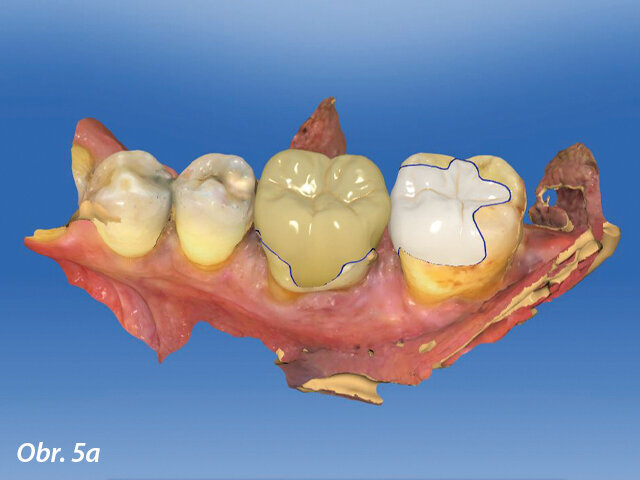

Ilustrační snímek z CAD výroby v distálním úseku horní čelisti.